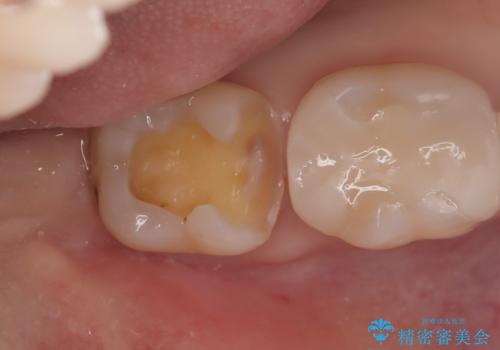

- 主訴:下の歯に入っている銀歯が笑うと目立つので白くしたい。

下顎臼歯部に入っている保険適用のメタルインレー(4箇所)を、審美性・適合性・清掃性の良いセラミックインレーにてやり替えました。